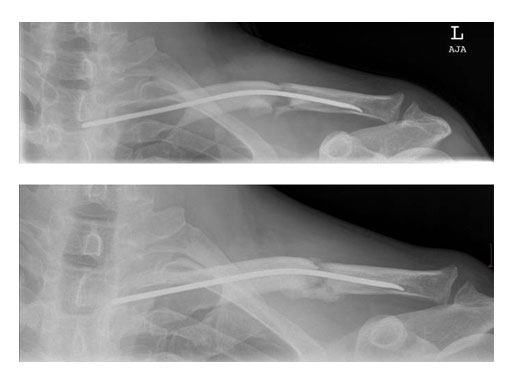

Case 2: 51 years, male, hit by tree